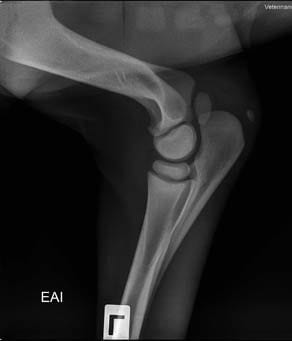

- Diagnóstico y seguimiento de cojeras

La radiología digital directa es una herramienta indispensable para el estudio v valoración en numerosas áreas de la atención veterinaria: valoración de cojeras, exámenes pre-compra, estudios radiológicos, diagnósticos más precisos en patologías, heridas, enfermedad…

Por eso nos mantenemos al día y nos renovamos con nuevos equipos de radiología digital directa que incorporan herramientas de diagnóstico y valoración con ventajas como:

- Herramientas de medidas más completas y potentes